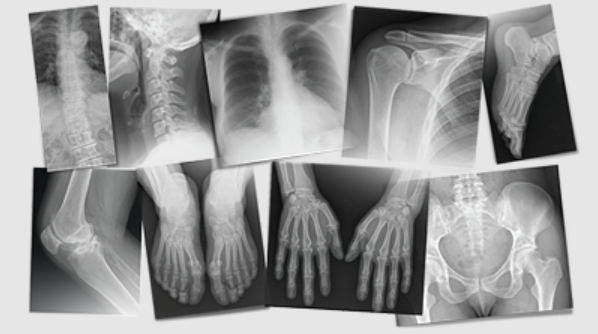

Diagnostic Testing Throughout Chicago: X-Rays, EMG’s & NCV’s

We use a range of diagnostic testing and imaging techniques throughout our conveniently-located Chicago clinics so our experts are able to address the source of your pain and classify your injury correctly.

X-rays are quick, noninvasive study useful in detection of fractures or injuries of the skeletal system. Radiographs (X-rays) can often detect soft tissue injuries, including diagnostic test for knee injuries or rotator cuff injuries in many cases.

The most common types of diagnostic tests are spine, abdomen, extremities, and chest